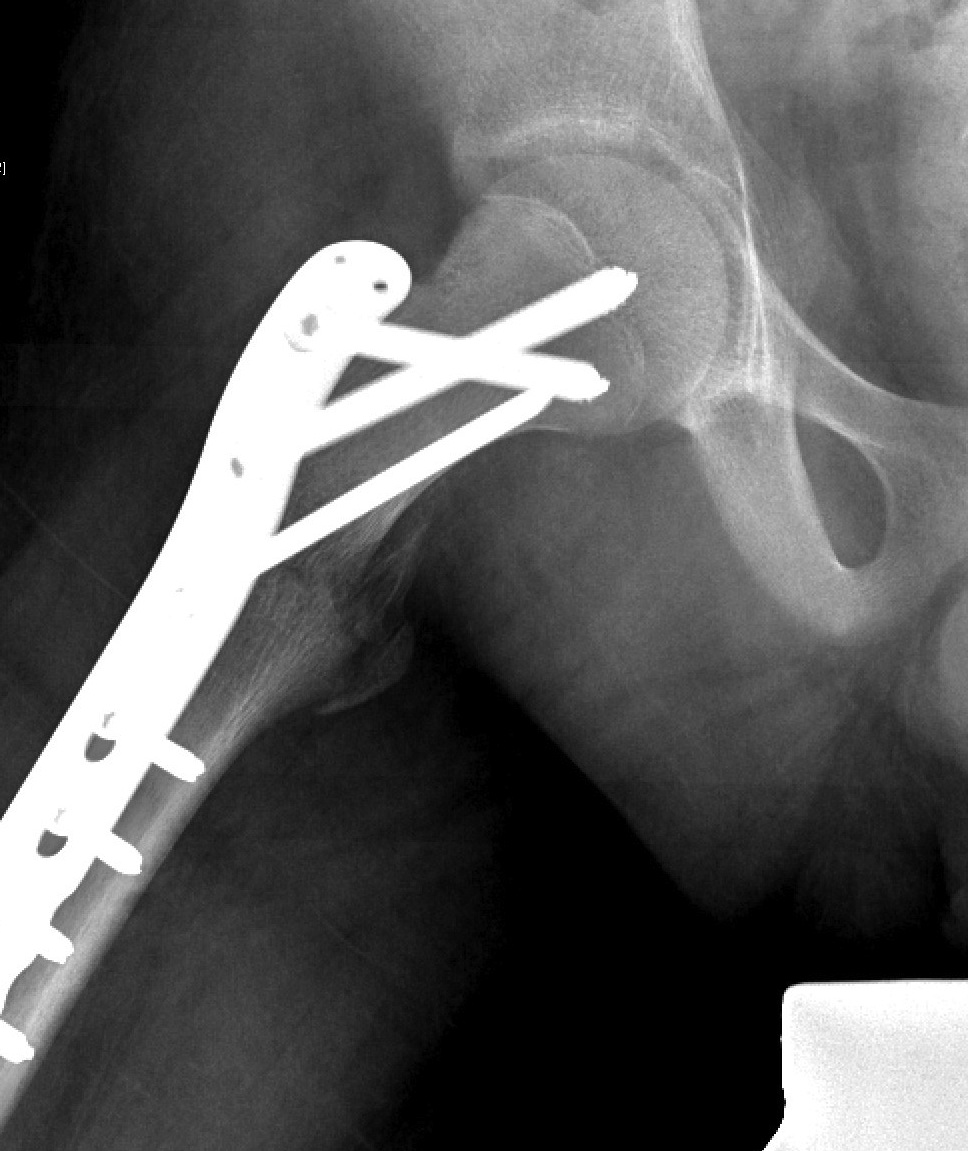

Fixation

- < 3 years K wires crossing physis

- > 3 cannulated screws crossing physis

Spica post op < 10 years

- < 3 years K wires

- > 3 cannulated screws / pediatic hip screw

- < 3 K wires

- > 3 pediatric hip screw